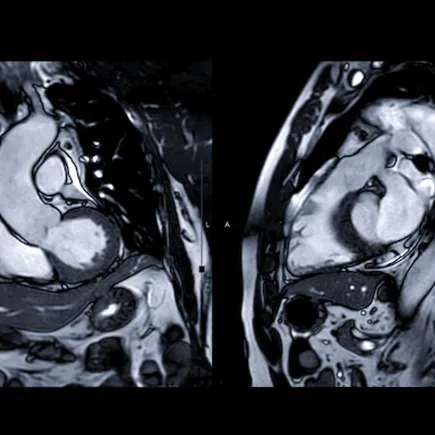

A cardiac magnetic resonance image (MRI), sometimes abbreviated as CMR, is a non-invasive imaging test that uses magnetic fields and radio waves to create images of the heart.